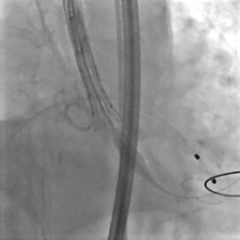

脱钩后造影,瓣膜0位,无反流

多体位确认,瓣膜稳定

外周血管造影,无损伤